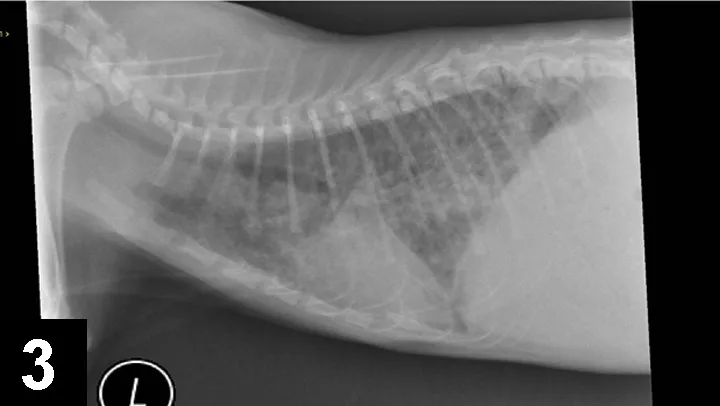

Parasite TestingLungworm and heartworm infections may cause similar signs. Lungworm infection, most common in young cats with exposure to outdoors and intermediate hosts, may cause clinical and radiographic signs

(Figure 3) similar to lower airway disease. Infection may be evaluated with a Baermann fecal sedimentation, or larva may be observed with airway cytology samples (Figure 4). Heartworm disease should be tested (via heartworm antigen and antibody test) in any cat with airway signs.

F__igure 3. Signs of lungworm infection that presented with signs similar to lower airway disease.